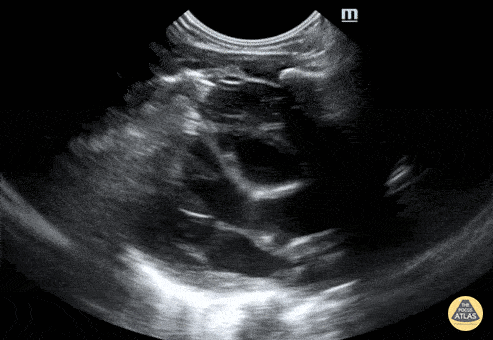

Normal Neonatal PSLA. Note thymus anteriorly. Contributor: Jaron Smith, MD Phoenix Children's Hospital